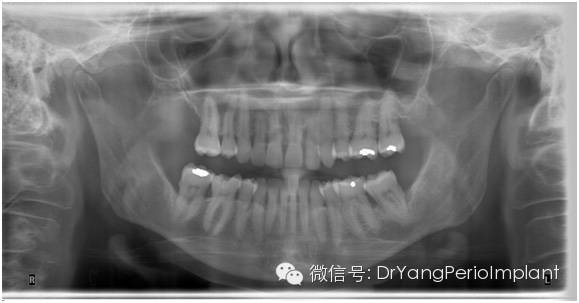

全景片通常用于判断患者有无颞下颌关节病变,因为它的图像变形率是25%不适于细节检查。

全景片,清晰显示关节。另外,对牙列有大致概念,但对细节,无法显示得象根尖片或咬翼片那样清晰(X光片取自笔者治疗过的病人).